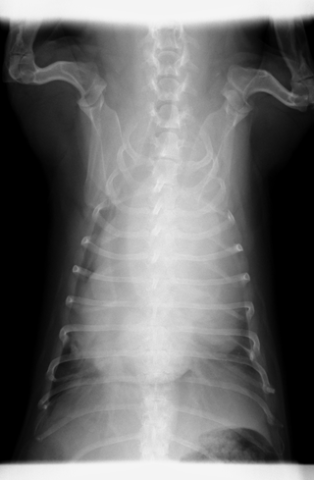

病院内ですぐに結果をお伝え出来る事もあれば、外部の検査センターへ依頼する場合もあります。細胞診の結果により、X線検査、超音波検査、CT検査、内視鏡検査、MRI検査を行いがんの進行の程度を明らかにし、外科手術、化学療法、放射線療法などの治療法を選択します。

手術計画

発生部位や腫瘍の種類やその挙動、手術後の機能について十分に検討の上、術式が決定されます。触知可能な境界部からサージカルマージンを決定します。

CTによる手術計画

血管走行や臓器との関係によりアプローチを決定します。